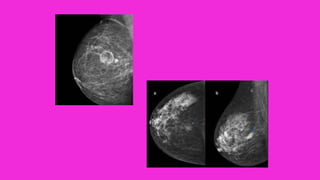

• Densidades . Las densidades mamográficas son

producidas la mayoría de las veces por carcinomas

invasivos, fibroadenomas o quistes.

• La mayor parte de las neoplasias son radiológicamente

más densas que el tejido mamario normal

entremezclado.

• La mamografía en las mamas densas pueden tener una

menor eficacia debido a la elevada cantidad de tejido

fibroso y escasez de tejido graso, ya que en estos

casos pueden quedar ocultos nódulos o tumoraciones al

ser unas mamas menos transparentes para los RX.